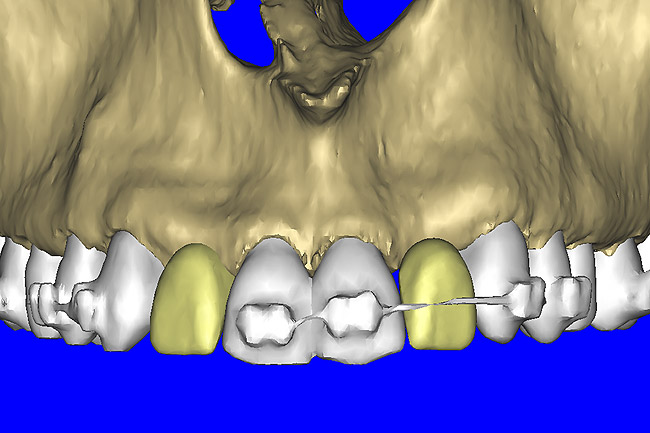

After the basic plan had been established, it was re-evaluated using interactive 3D images. The reconstructed 3D view of the maxilla clearly illustrated the extent of the bilateral facial concavities, and the root eminences of the adjacent and posterior teeth (Figure 7A). The placement of the virtual implants then was evaluated to ensure that the facial cortical plate was not perforated (Figure 7B). The implants were labeled individually as “7” and “10,” with the simulated yellow abutment projection indicating the facial-lingual inclination through the bone to the level above the incisal edge of adjacent teeth. The ability to gain a better understanding of these individual root forms can not be underestimated. The dental literature has suggested certain parameters for placing implants near teeth and implants next to other implants. However, there is little scientific 3D documentation to support these suggested rules.5-10 The use of an interactive treatment-planning software application permits closer scrutiny of previously difficult-to-visualize areas, and can now be used to redefine perceptions of spatial positioning of implants, especially when in close proximity to natural tooth roots, vital anatomy, and adjacent implants.27-29

Figure 7a  The 3D reconstruction showed (A) the facial concavities and root eminences, and allowed (B) for evaluation of virtual implant placement to ensure the facial cortical plate was not perforated.

Figure 7a

Figure 7b  The 3D reconstruction showed (A) the facial concavities and root eminences, and allowed (B) for evaluation of virtual implant placement to ensure the facial cortical plate was not perforated.

Figure 7b